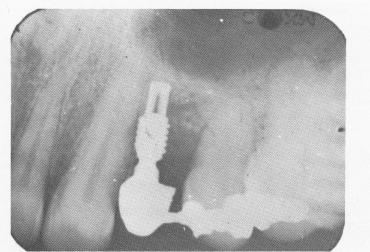

Fig. 8-46. A periapical postoperative radiograph of the completed case.

3 Xray of case of stabilized upper endosseous implant with inlay